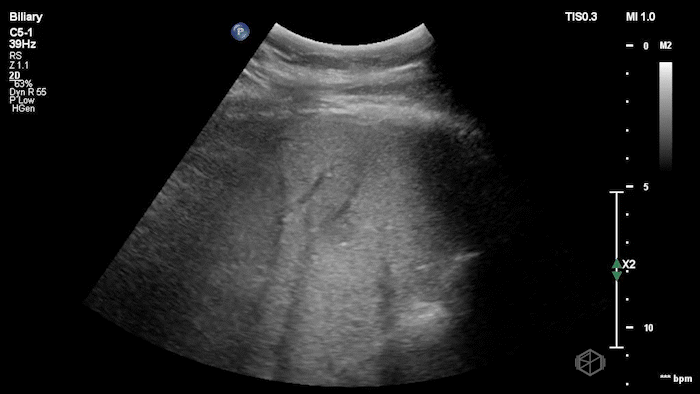

Dr. Mendelow was scanning a late 20’s male with acute epigastric and right upper quadrant pain with nausea and vomiting. He was significantly hypertensive and tachycardic likely due to pain. On exam the patient had a notable Murphy’s sign.

Dr. Mendelow performed a POCUS within 5 minutes that showed the following:

This scan shows a gallbladder filled with stones as indicated by the bright hyperechoic stones with shadowing posteriorly and almost no visible gallbladder wall lumen. This is consistent with a Wall-Echo-Shadow (WES) sign or configuration. The patient had a significantly elevated lipase and total bilirubin indicating gallstone pancreatitis. Radiology ultrasound resulted 90 minutes later with similar findings.

Diagnosis: Gallstone pancreatitis; WES sign